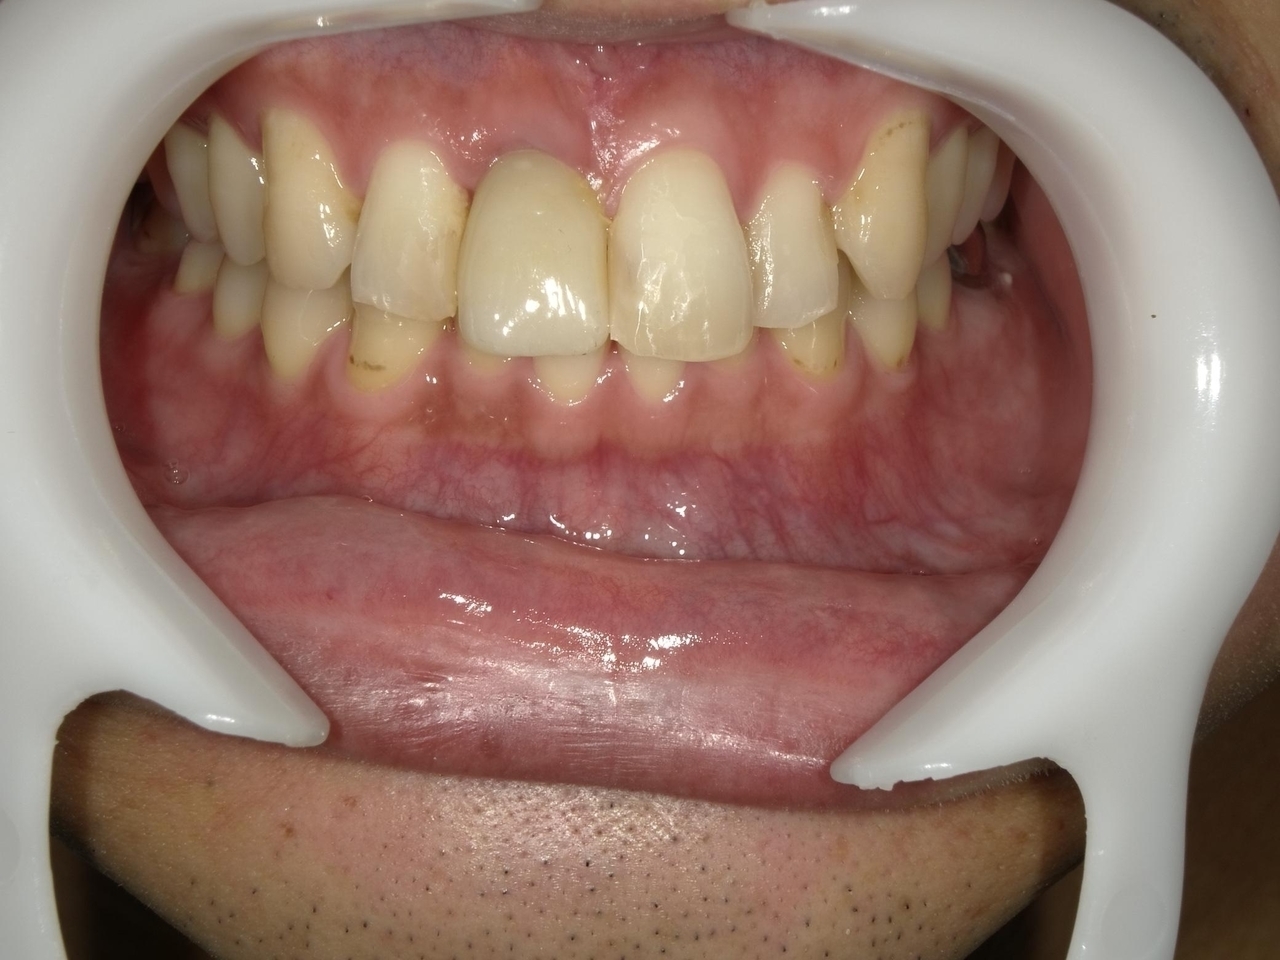

4.右上4~7番が重度に動揺しているために、抜歯した当日にインプラントを埋入して、3か月で最終的な歯を完成させたケース

Before

After

K・S様 女性 60代

症状としては、 右上4から7番までのすべての歯の著しい動揺があり、食事が困難であった。

治療法としては、患者様は、患者様が3か月以内の治療完了を望んでいたために、炎症が若干あったが、右上4から7番ぼすべての抜歯を行い、右上4番(抜歯即時埋入)、右上6番(上顎洞までの骨がほとんどないため、グラフトレスサイナスリフト施行)にインプラントを1回法で手術を終え、2か月半後にインプラントの状態が安定したために、3か月で上部構造の、右上456のジルコニアブリッジを装着して、治療を終えています。

治療結果としては、抜歯したと同時にインプラントを埋入することで、抜歯した穴が自然に治る過程で、インプラントの骨結合と組織の治癒が同時に行われるために、3か月という治療期間で治療を終了することができたことと、機能面・審美面でも回復を行うができた。また、右上6番に関しては、グラフトレスサイナスリフトを行うことで、従来のサイナスリフトに比べ、約9か月早く治療を終えることができました。

治療の期間・回数:約3か月、インプラント抜歯即時埋入から最終補綴物装着まで8回

治療の価格:792000円(税込)

治療費の内訳:インプラント基本料(フィックスチャー(メガジェンインプラントANYONE使用) 及び手術費用、投薬費用、レントゲン費用、インプラント上部費用(アバットメントおよびジルコニアクラウンの費用用)330000円×2 660000円(税込み)。オプション、抜歯即時埋入加算(人工骨費用を含まず)5500円×2 11000円(税込み)右上5ジル9コニアブリッジのポンテック費用 88000円 右上6グラフトレスサイナスリフト費用 33000円(税込み

治療のリスクや副作用:手術後に、痛みや腫れ、出血、合併症などを引き起こす可能性があります。噛む感覚がご自身の歯と異なる場合があります。見た目がご自身の歯と異なる場合があります。手術後にメインテナンスを継続しないと、インプラントが抜け落ちる可能性があります。